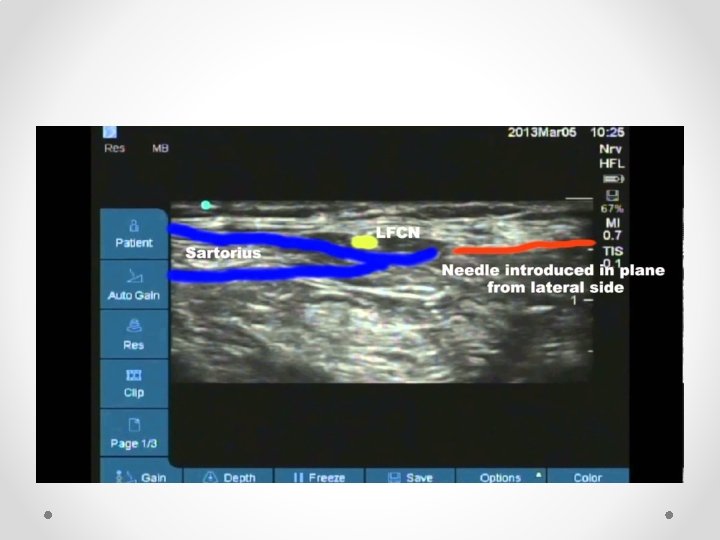

Lateral Femoral Cutaneous nerve block